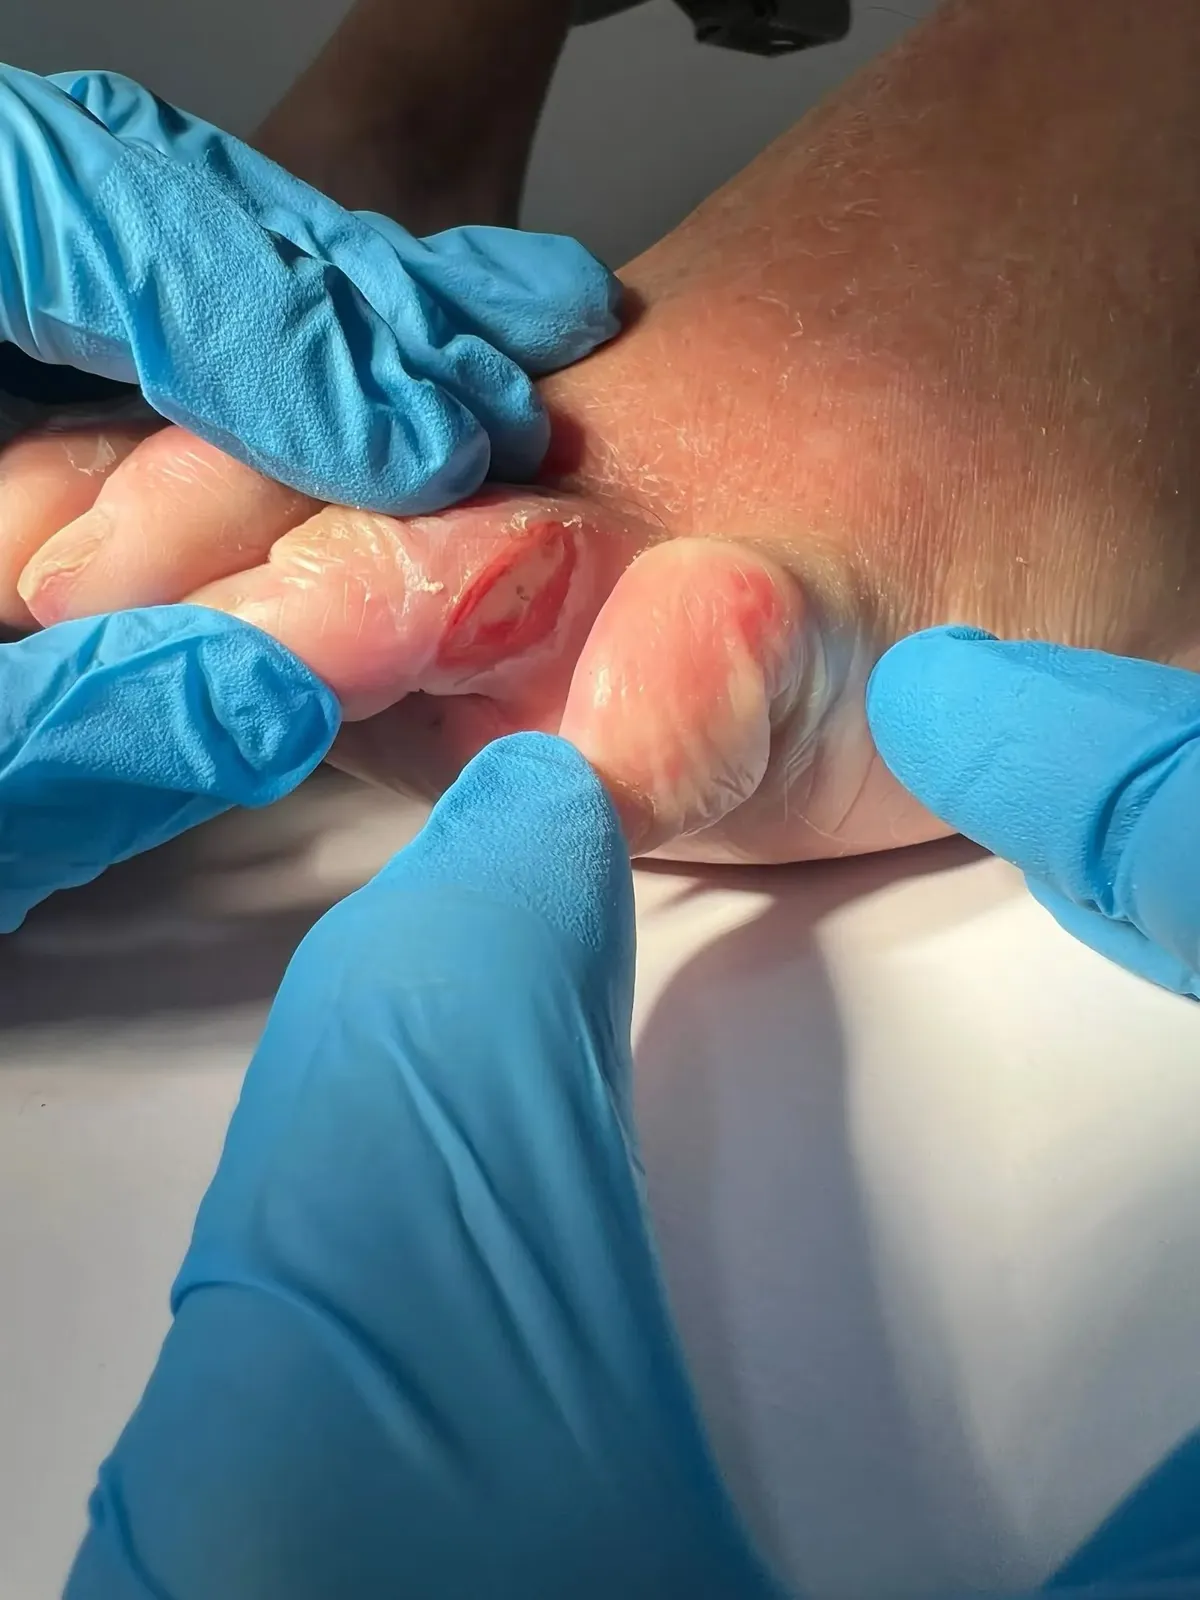

La Exploración Física: Siguiendo las Pistas

La palpación fue reveladora. Presionamos la zona del espolón calcáneo en la planta del pie: sin dolor significativo. Palpamos la inserción de la fascia plantar: molestia leve, pero nada dramático.

Pero cuando presionamos la parte posterior del talón, justo donde el tendón de Aquiles se inserta en el hueso…

“¡Ay! Ahí, ahí exactamente. Eso es lo que me duele”, exclamó María.

El dolor estaba localizado en la bursa retrocalcánea, una pequeña bolsa llena de líquido que actúa como amortiguador entre el tendón de Aquiles y el hueso calcáneo. Y el tendón de Aquiles también estaba sensible a la palpación.

La Ecografía: Desvelando el Verdadero Problema

Las radiografías muestran huesos, pero no pueden ver tejidos blandos como bursas o tendones. Por eso la ecografía podológica es fundamental en estos casos.

Al colocar el transductor ecográfico en la parte posterior del talón de María, la imagen fue clarificadora:

- Bursa retrocalcánea claramente engrosada con líquido en su interior (señal inequívoca de inflamación)

- Tendinosis leve del tendón de Aquiles distal con pérdida del patrón fibrilar normal

- El espolón calcáneo visible: presente, sí, pero sin signos inflamatorios alrededor, como un espectador silencioso

“¿Ve esta zona oscura, María? Esto es líquido inflamatorio en su bursa. Y aquí, el tendón de Aquiles muestra signos de sufrimiento. El espolón está ahí, pero no es el problema”.